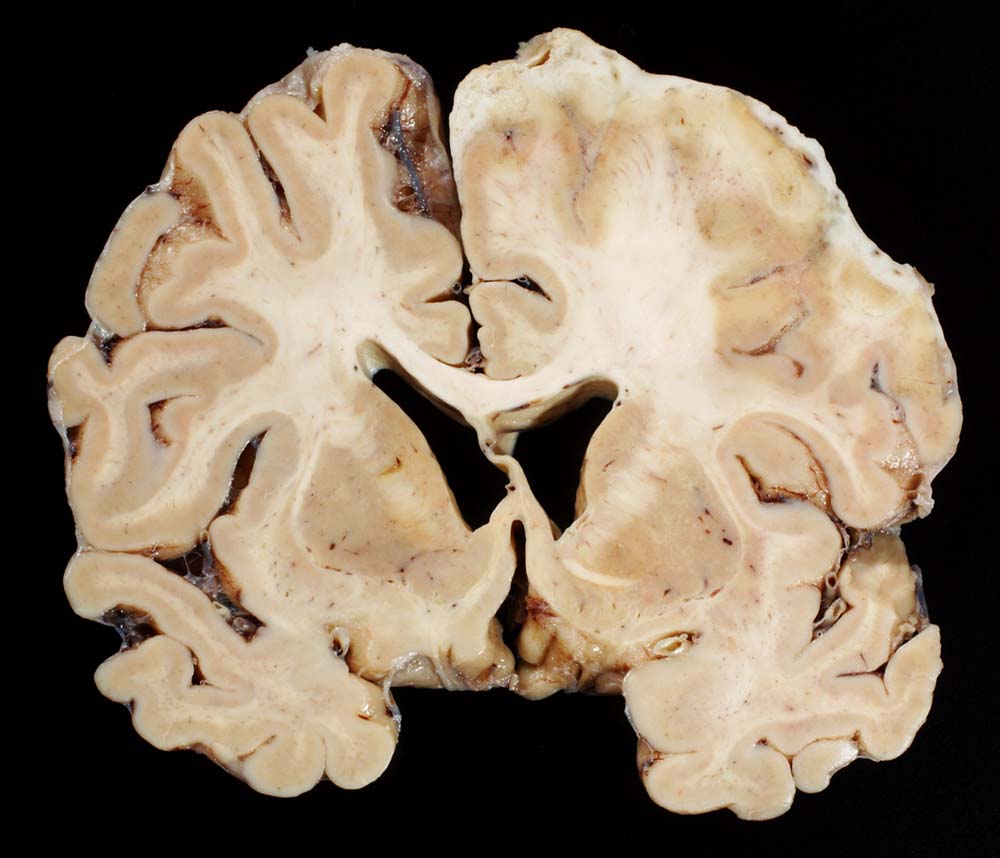

PathoPic – image database / PathoPic ID 8906 - Eitrige Meningoenzephalitis (Pneumokokken), subdurales Empyem

Eitrige Meningoenzephalitis (Pneumokokken), subdurales Empyem

Die rechte Hemisphäre ist überzogen von einer Eiterschicht und der angrenzende Cortex ist nekrotisch.

Chronischer Alkoholabusus. Diabetes mellitus. Hospitalisation in somnolentem febrilem Zustand im Rahmen einer Pneumokokkensepsis. Klinisch Ausschluss einer Endokarditis. Ischämie rechts frontotemporal mit schlaffer Hemiparese links. Unklarer neurologischer Zustand vermutlich metabolisch-toxischer Genese. Rhabdomyolyse bei St.n. Liegetrauma. Niereninsuffizienz. Tracheotomie wegen respiratorischer Verschlechterung.